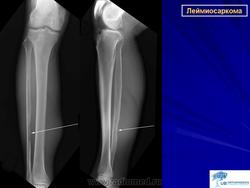

Лейомиосаркома.

High-grade leiomyosarcoma in the left thigh